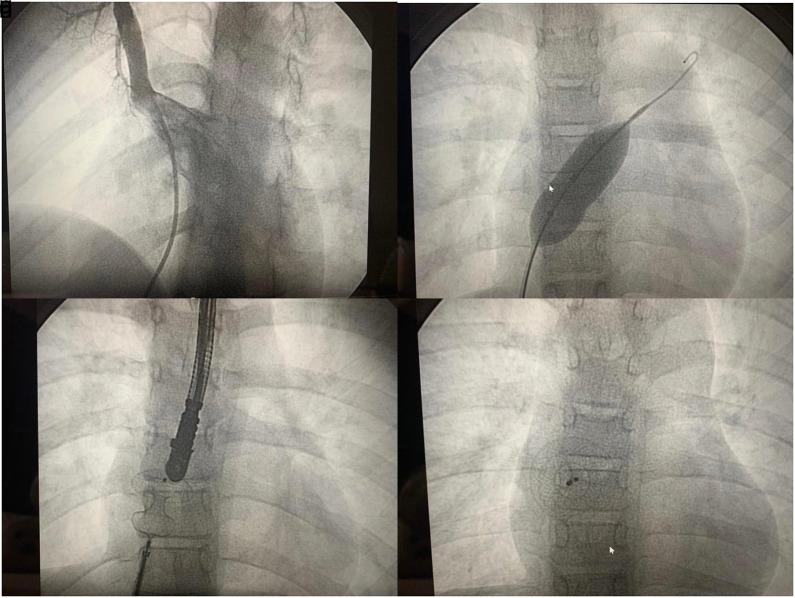

儿童房间隔缺损的经导管封堵术:单中心经验及中期随访结果

Transcatheter Closure of Atrial Septal Defect in Children: Single-Center Experience, Mid-Term Follow-up Results.

Atrial septal defect is a congenital heart disease usually diagnosed in childhood. This study aimed to evaluate the mid-term follow-up results of patients who underwent trans- catheter closure of atrial septal defect by comparing the devices and methods used in the procedure and investigating the complications of this procedure in children.

MATERIALS AND METHODS

This study evaluated 232 patient files retrospectively. Of the 232 patients, 24 were excluded from the study due to missing files or data. Also, patients with multi-fenestrated atrial septal defect and aneurismatic septal tissue were excluded from the study. The following data were evaluated: follow-up time, patient complaints, symptoms, trans- thoracic echocardiography, and transesophageal echocardiography findings (if performed), the size of the defect as measured by balloon-sizing, the size of the device used in the proce- dure, and major and minor complications.

RESULTS

The study included 208 children who were diagnosed with atrial septal defect. The mean age of the patients was 88.0 ± 56.5 months. Of the patients, 170 (81.7%) had no com- plaints. The success rate of the procedure was found to be 95.7%. While device embolization was the most common major complication, arrhythmia was the most common minor complica- tion. The complication rate was statistically different according to the device type used in the procedure.

CONCLUSION

Transcatheter closure of atrial septal defect is a safe method for atrial septal defect closure in pediatric patients. The study found that defect diameters measured by differ- ent methods were not correlated with each other. The procedure complication rates differed according to device type.